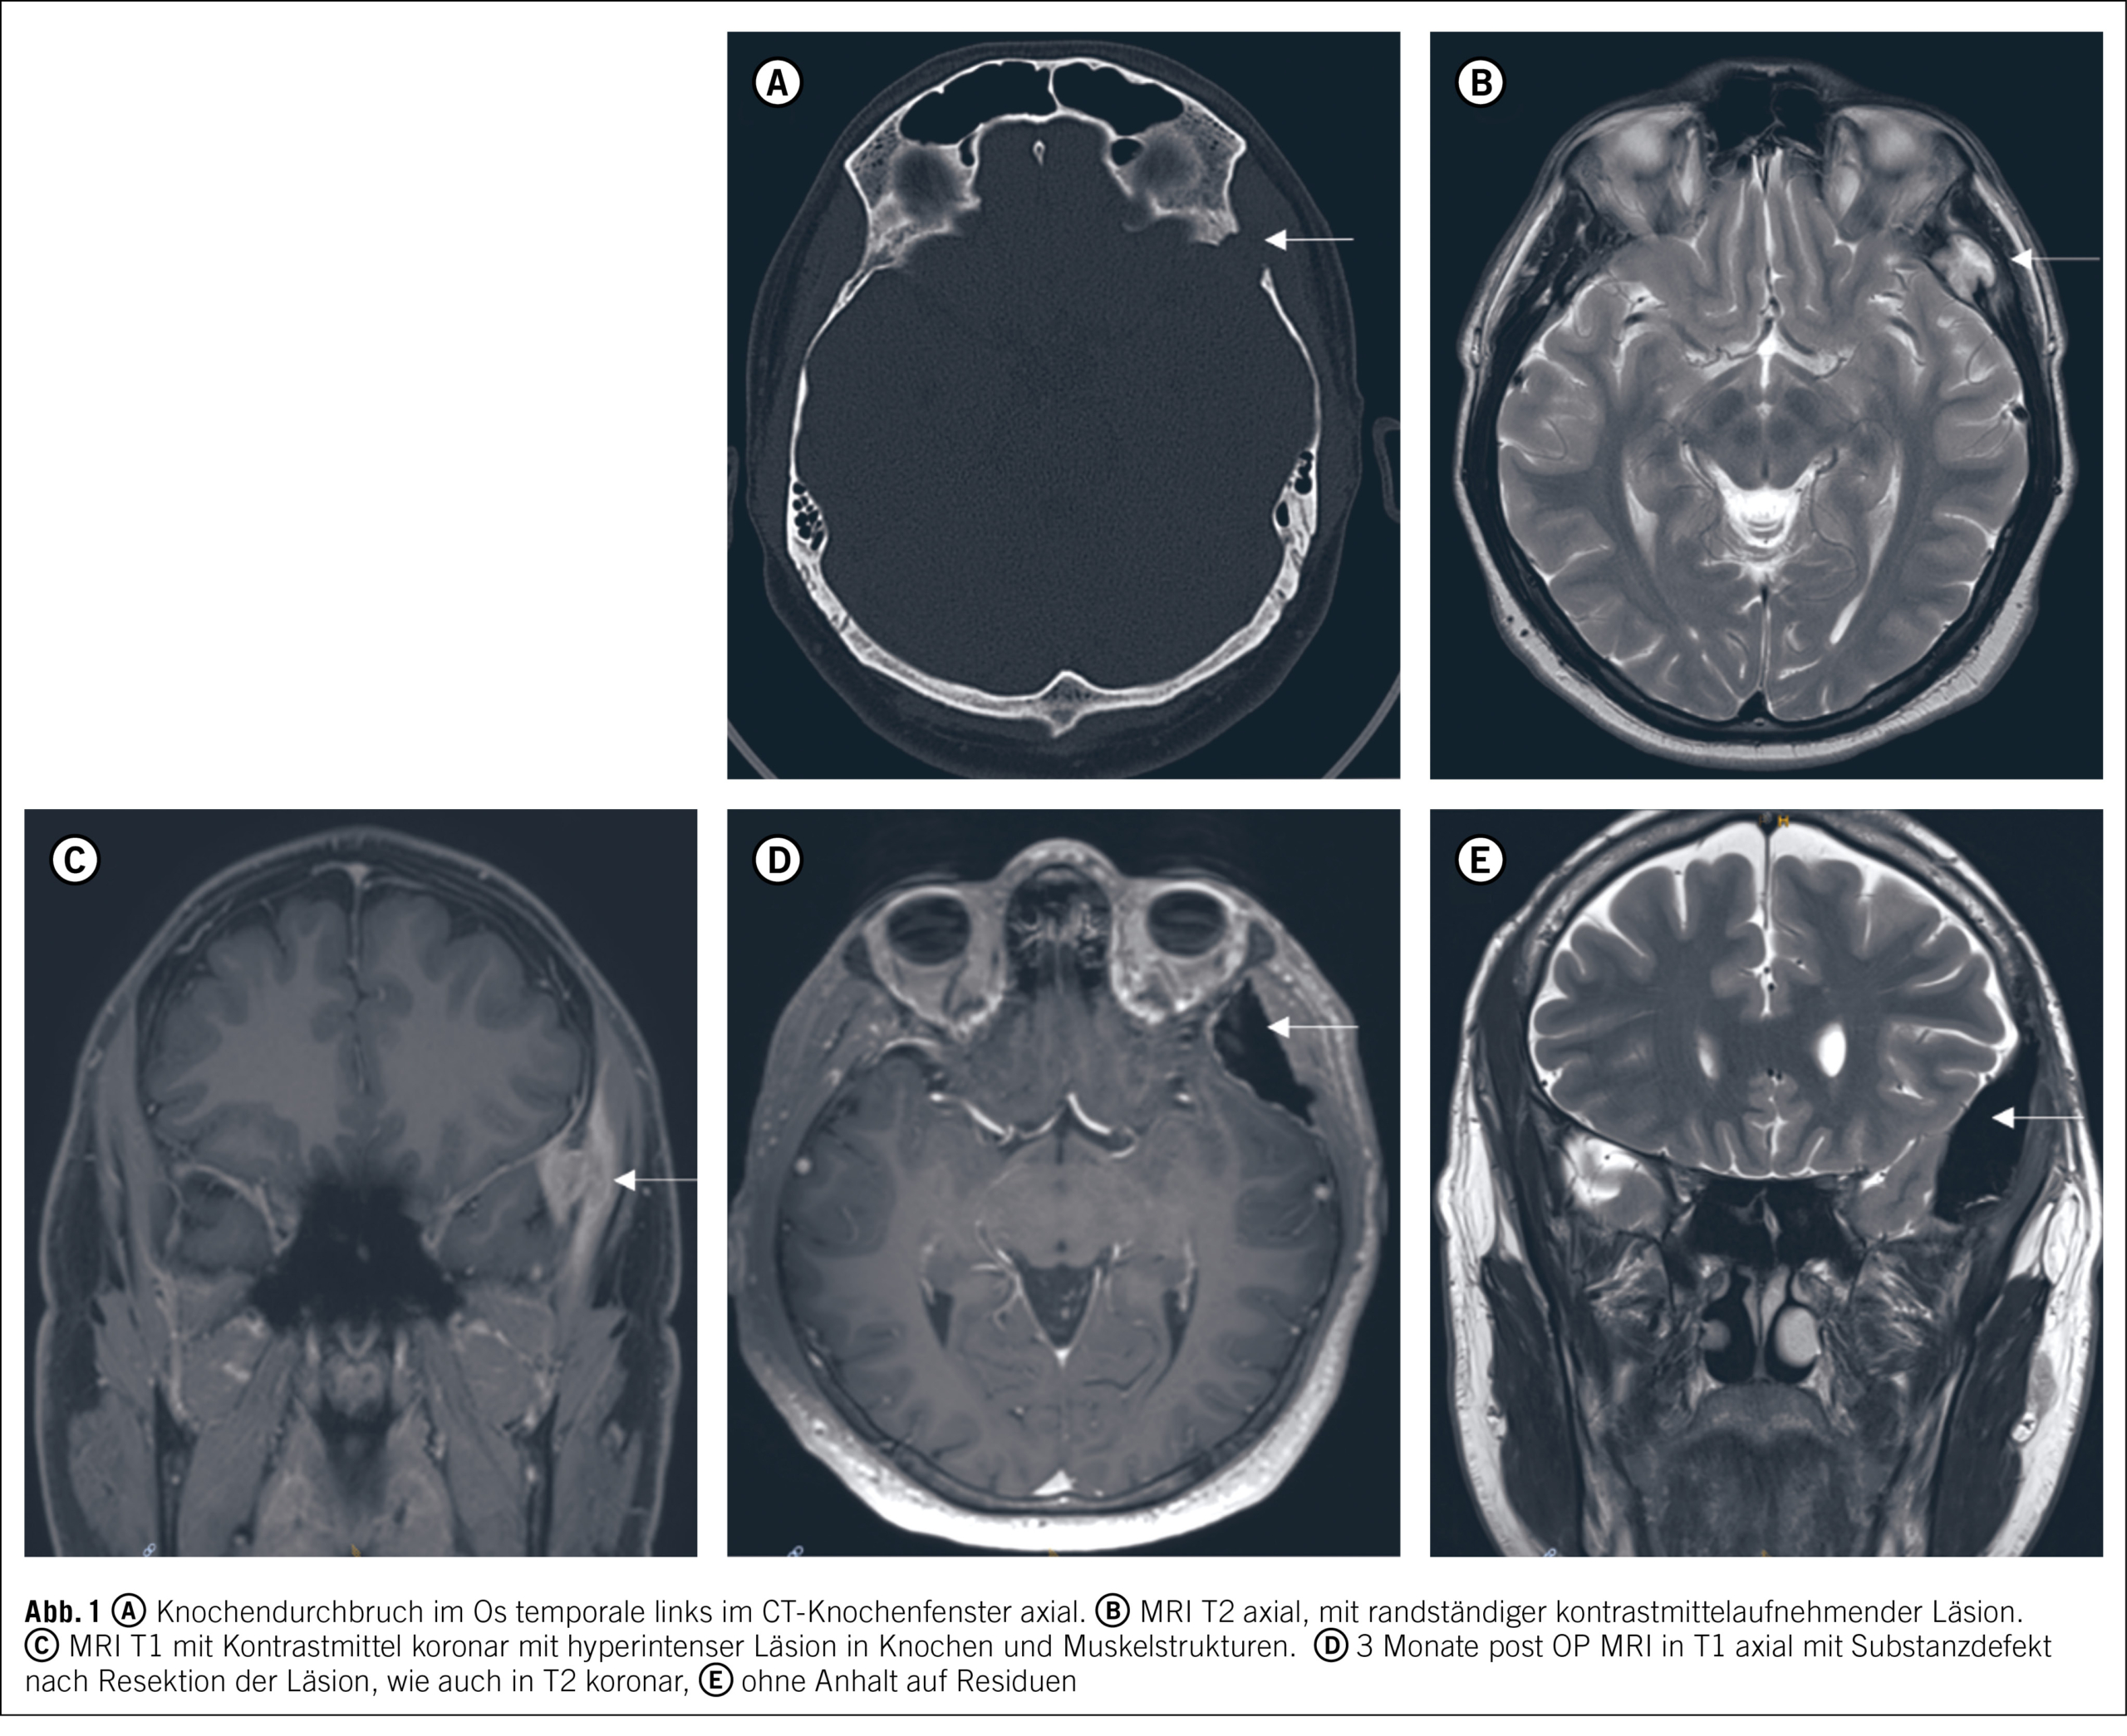

Zur Diagnosesicherung ist eine histologische Aufarbeitung unumgänglich. Aufgrund des umschriebenen und chirurgisch gut zugänglichen Befundes wird der Entscheid zur mikrochirurgischen Komplettresektion der Läsion mit Rekonstruktion der Schädelkalotte gestellt. Der Eingriff kann komplikationslos durchgeführt und das Resektat der neuropathologischen Aufarbeitung zugeführt werden (Abb. 2 A).

Es zeigt sich ein perioperativer komplikationsloser Verlauf ohne fokal-neurologische Defizite. In der postoperativen MRI zeigt sich eine Komplettresektion, und der Patient ist beschwerdefrei (Abb. 1 D und E). Eine vier Monate nach der Operation durchgeführte F-18-Fluorethyltyrosin, Radionuklid (FET) Positronen-Emissions-Tomographie (PET) CT gibt keine Hinweise auf weitere Läsionen (Abb. 2 B)